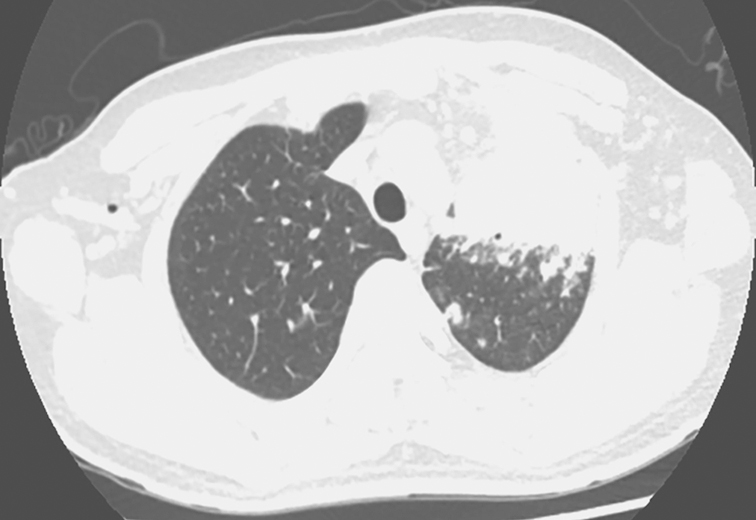

2014年8月6日胸部CT:左肺上叶支气管呈术后改变,支气管残端显示不清。左上叶前段可见大片状密度增高影,边缘模糊,平扫CT值46HU,增强后CT值73HU。双肺野内和胸膜下可见散在大小不等结节状密度增高影,边缘模糊,较大者位于右下叶背段,大小约2.4cm×1.8cm,气管、支气管通畅,纵隔内可见多个小淋巴结,较大者直径8mm。无胸腔积液征象(图1、图2)

图1 发病第3个月胸部CT表现

胸部CT可见左上肺大片高密度影伴空洞